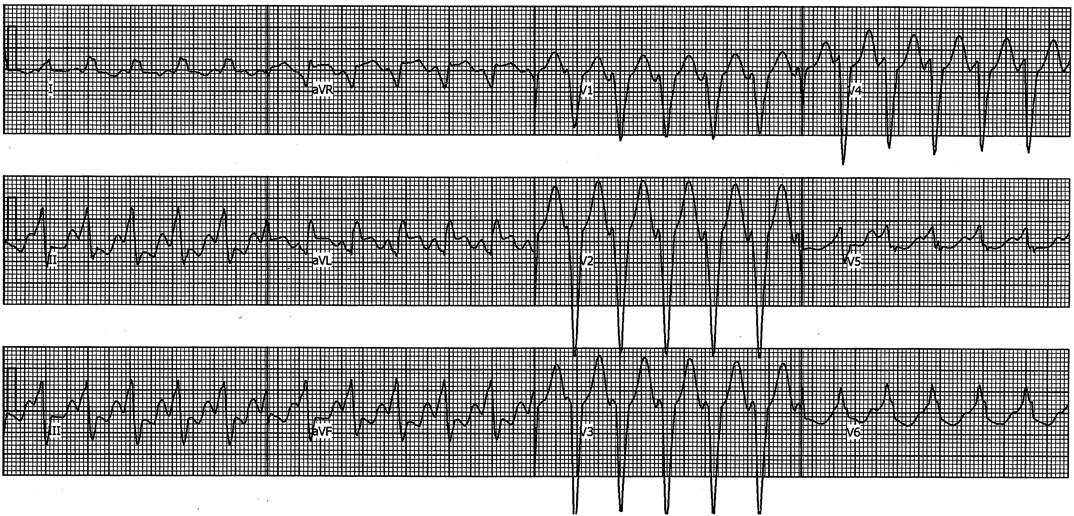

Pediatric Cardiology and Cardiac Surgery 33(5): 385-394 (2017)

Fig. 5 Electrocardiogram of monomorphic ventricular tachycardia in a patient with repaired tetralogy of Fallot and a heart rate of 140 beats/min. The QRS morphology exhibited a left bundle-branch block pattern and inferior axis